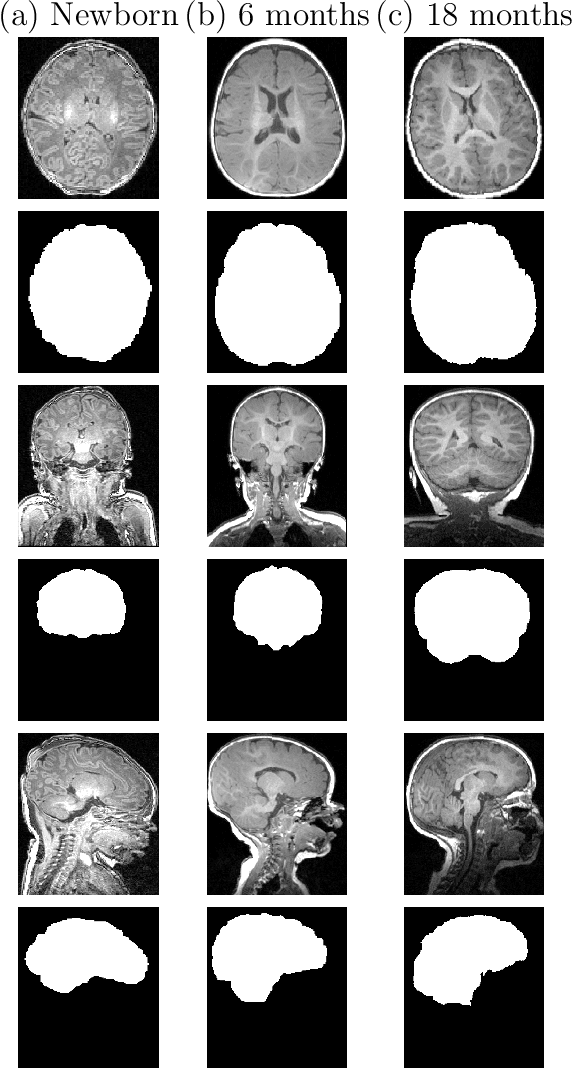

Abstract:Skullstripping is defined as the task of segmenting brain tissue from a full head magnetic resonance image~(MRI). It is a critical component in neuroimage processing pipelines. Downstream deformable registration and whole brain segmentation performance is highly dependent on accurate skullstripping. Skullstripping is an especially challenging task for infant~(age range 0--18 months) head MRI images due to the significant size and shape variability of the head and the brain in that age range. Infant brain tissue development also changes the $T_1$-weighted image contrast over time, making consistent skullstripping a difficult task. Existing tools for adult brain MRI skullstripping are ill equipped to handle these variations and a specialized infant MRI skullstripping algorithm is necessary. In this paper, we describe a supervised skullstripping algorithm that utilizes three trained fully convolutional neural networks~(CNN), each of which segments 2D $T_1$-weighted slices in axial, coronal, and sagittal views respectively. The three probabilistic segmentations in the three views are linearly fused and thresholded to produce a final brain mask. We compared our method to existing adult and infant skullstripping algorithms and showed significant improvement based on Dice overlap metric~(average Dice of 0.97) with a manually labeled ground truth data set. Label fusion experiments on multiple, unlabeled data sets show that our method is consistent and has fewer failure modes. In addition, our method is computationally very fast with a run time of 30 seconds per image on NVidia P40/P100/Quadro 4000 GPUs.